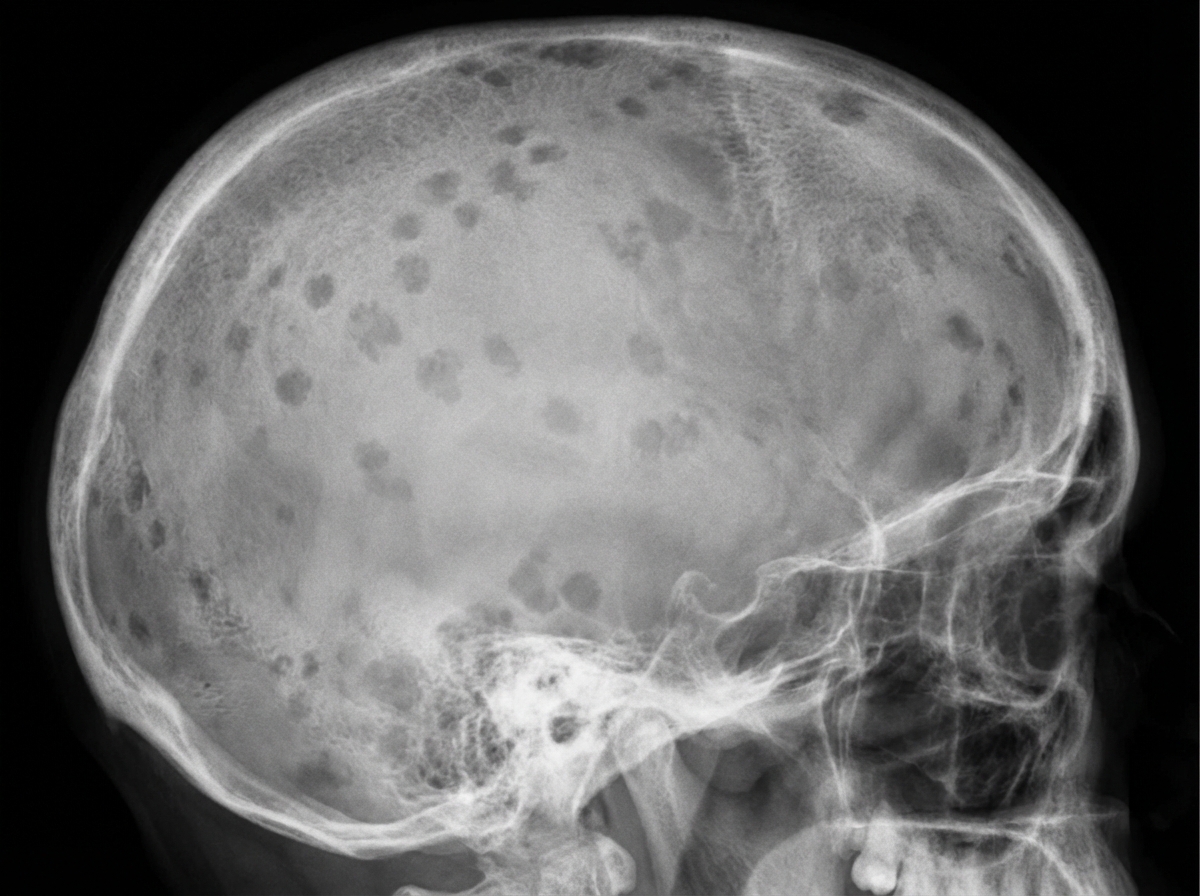

A 71-year-old African American man is brought to the emergency department with a worsening productive cough and dyspnea for 2 days. He has had generalized bone pain for 2 months. He was admitted for pyelonephritis last month. He also received outpatient treatment for pneumonia almost 2 months ago. Over the past 2 months, he has been taking over-the-counter ibuprofen for pain as needed. He appears anxious. The vital signs include: temperature 38.8°C (101.8°F), pulse 95/min, respiratory rate 20/min, and blood pressure 155/90 mm Hg. The conjunctivae are pale. Crackles are heard in the right lower lobe. The cardiac examination shows no abnormalities. The laboratory studies show the following: Hemoglobin 9 g/dL Mean corpuscular volume 95 μm3 Leukocyte count 13,500/mm3 Segmented neutrophils 75% Lymphocytes 25% Platelet count 240,000/mm3 ESR 85 mm/hr Serum Na+ 135 mEq/L K+ 4.2 mEq/L Cl− 113 mEq/L HCO3− 20 mEq/L Ca+ 12.4 mg/dL Albumin 4 g/dL Urea nitrogen 38 mg/dL Creatinine 2.2 mg/dL A chest X-ray shows a right lower lobe opacity and blurring of the ipsilateral diaphragmatic dome. Skull and pelvic X-rays are performed (see image). Which of the following is the most likely underlying cause of this patient’s recent infections?